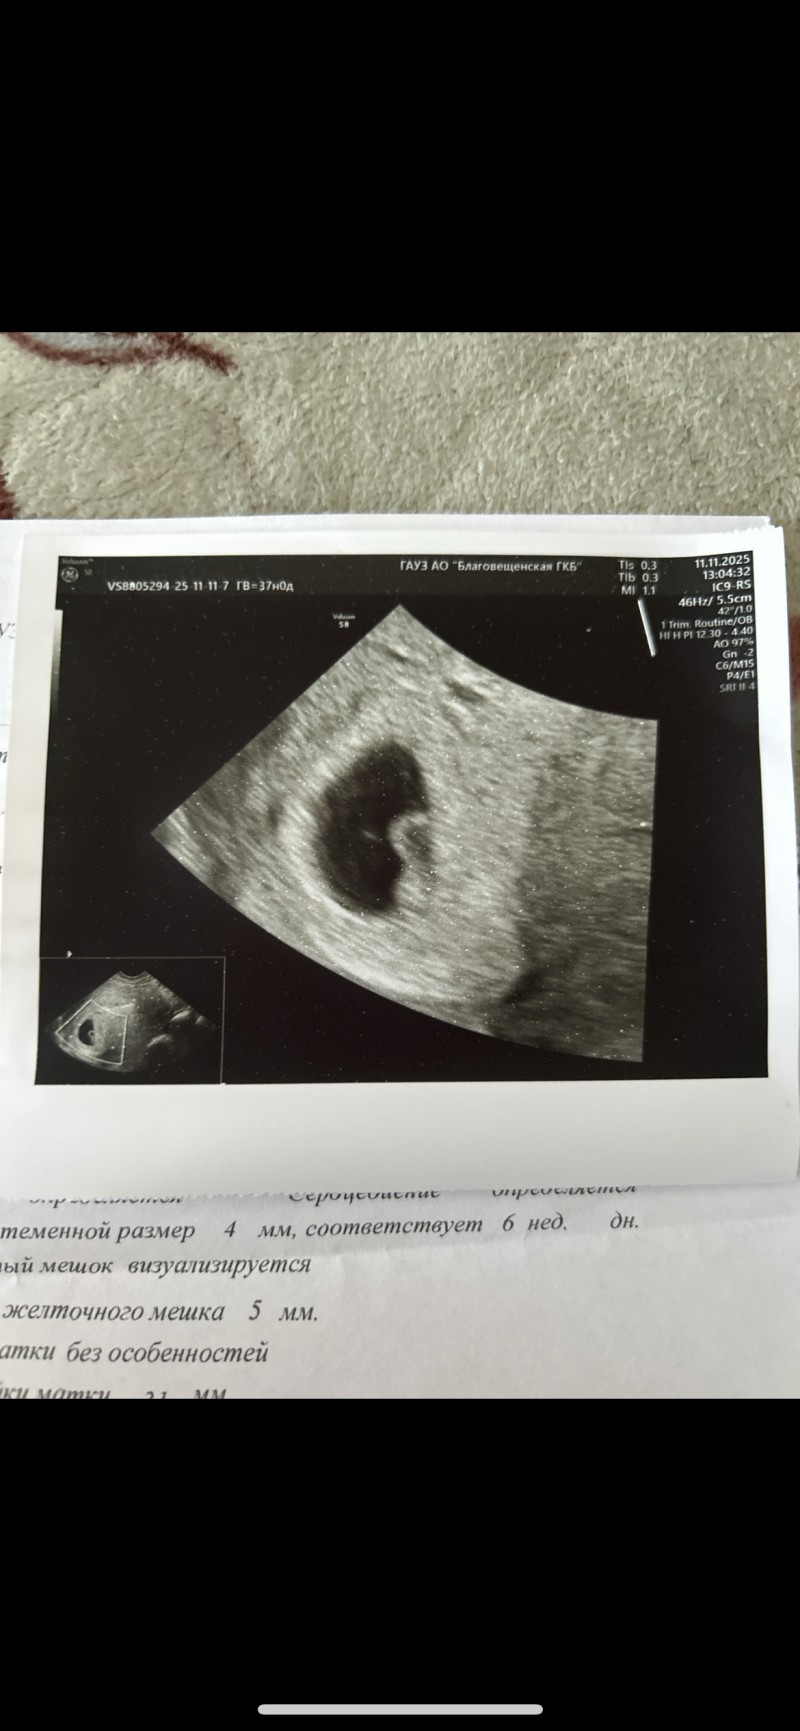

image